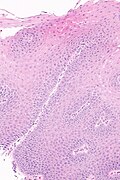

Template:Px Micrograph showing histology compatible with gastroesophageal reflux disease. H&E stain. | |

| LM | basal cell hyperplasia (> 3 cells thick or >15% of epithelial thickness), papillae elongated (papillae reach into the top 1/3 of the epithelial layer), inflammation, esp. eosinophils, lymphocytes with convoluted nuclei ("squiggle cells"), +/-intraepithelial edema, +/-apoptotic cells, +/-glycogenation |

| LM DDx | intestinal metaplasia (Barrett's esophagus), eosinophilic esophagitis, acute esophagitis |

Microscopic

Features:

- Basal cell hyperplasia;[5] > 3 cells thick or >15% of epithelial thickness.

- Papillae elongated; papillae reach into the top 1/3 of the epithelial layer.[6]

- Inflammation, esp. eosinophils, lymphocytes with convoluted nuclei ("squiggle cells").

- +/-Intraepithelial edema.

- +/-Apoptotic cells.[7]

- +/-Glycogen - cytoplasm cleared (white).[8]

- Gastroesophageal reflux disease -- low mag.jpg

GERD - low mag.